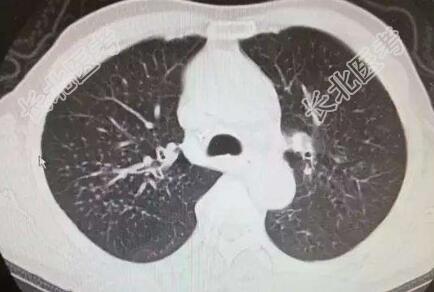

辅助检查:心电图:窦性心律,肺型P波,T波改变;心脏彩超:主动脉瓣退变伴少量反流,左室舒张功能减退;颅脑+胸部+颈部CT:双侧基底节区、丘脑、放射冠多发新陈梗塞灶,老年性脑改变,C3-4C4-5椎间盘突出,C6椎体后缘增生,右上肺结节影。